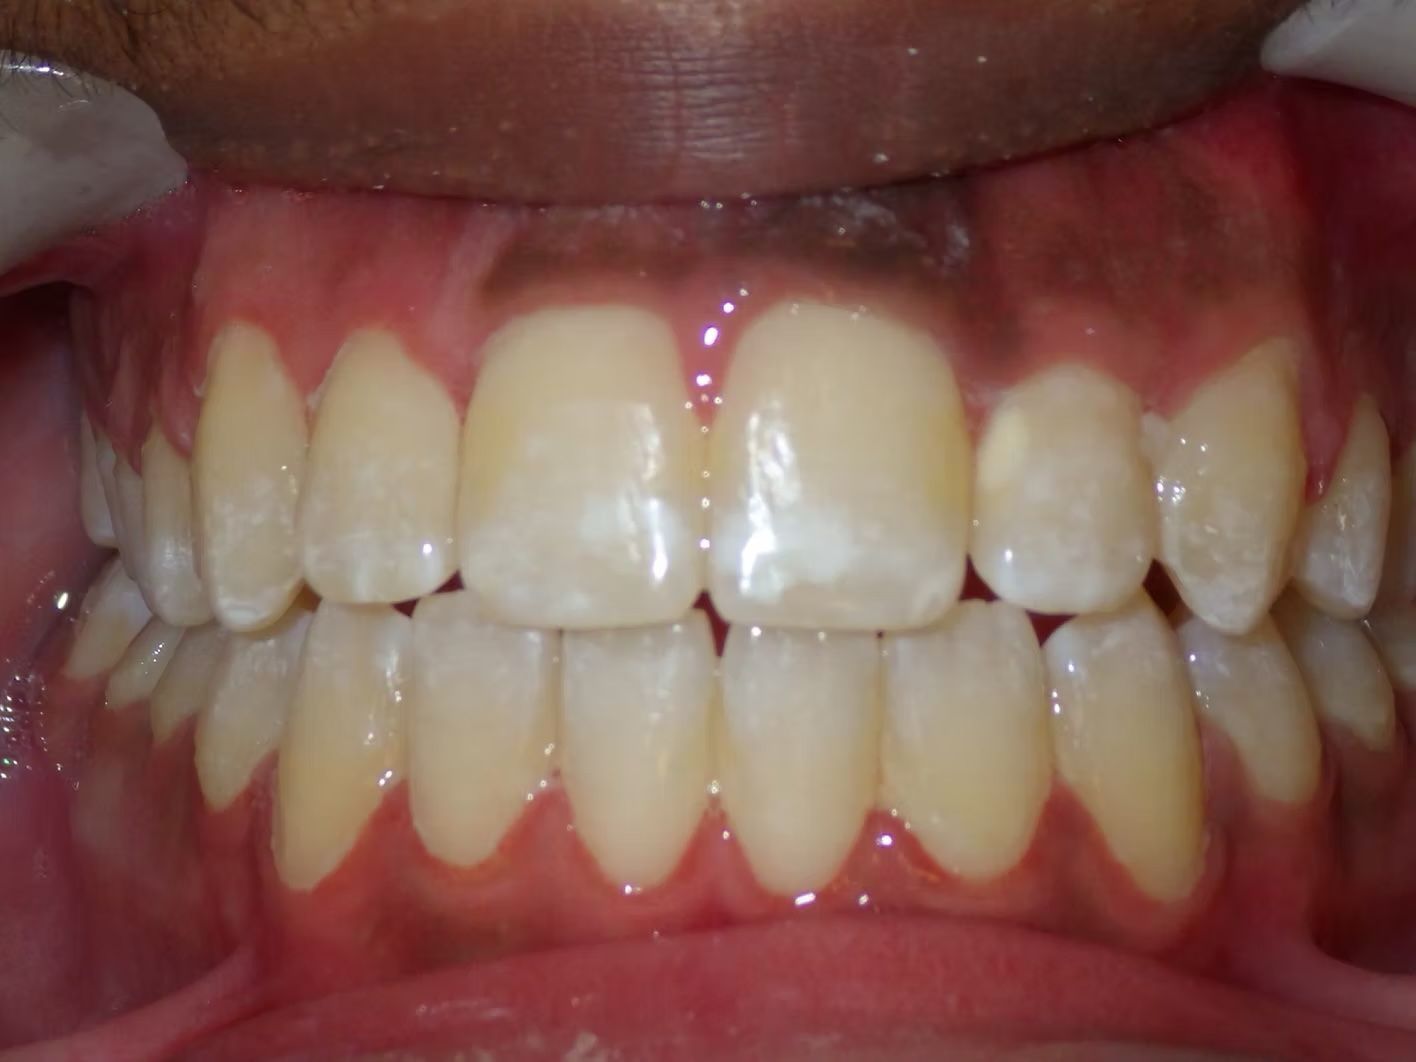

Johntavious

Johntavious didn't like that one of his lower teeth was set behind the rest. He went to many orthodontists who told him to extract the tooth or multiple teeth to correct the alignment. Johntavious and his parents didn't want to go that route and wanted to try to align the teeth without the extraction. Dr. Bret was able to successfully straighten the upper and lower teeth - fit the tooth that was back into the dental arch and make Johntavious and his parents really happy.